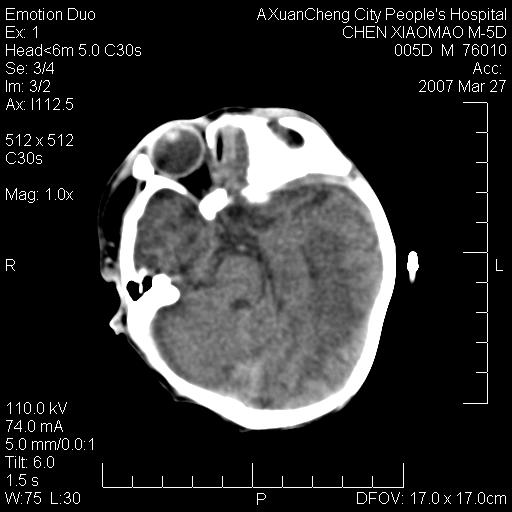

缝是正常的,但患儿有hie

大家看看可有hie ?还有左侧枕部胡形高密度ct为45~53hu,可有硬膜下血肿?

hie.............